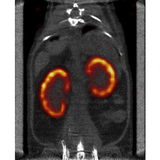

The X-CUBE is our high throughput CT “work horse”. It allows for fast whole body mouse and rat CT imaging at extremely low dose and excellent soft tissue contrast.

Light weighted thanks to a self-shielded imaging unit it is a truly mobile in vivo scanner. Advanced workflows such as gated and dynamic contrast enhanced imaging can be achieved in a functional and integrated set up. Our iterative reconstruction techniques are available in standard as well as expert user mode. Intuitive and wireless acquisition software combined with our multimodal small animal bed allow for easy and modular multimodal imaging along with the γ-CUBE (SPECT) and β-CUBE (PET).